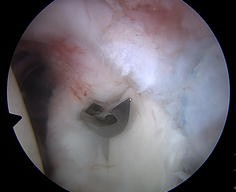

Fig. 1